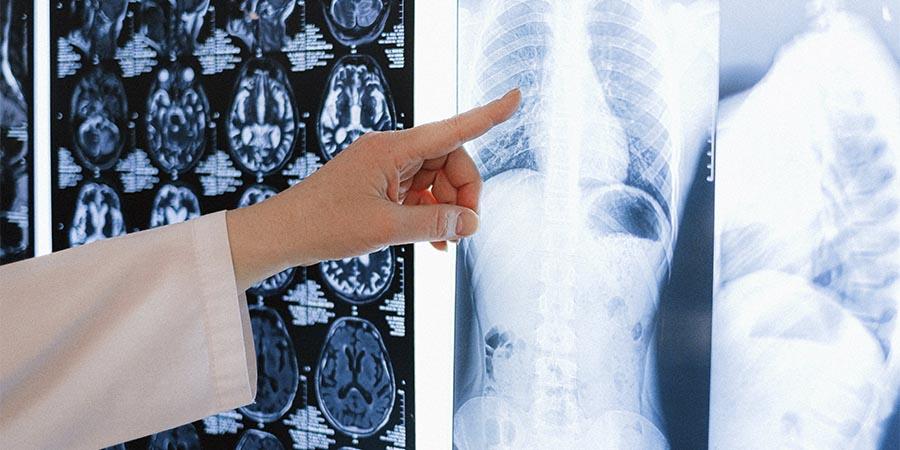

La sacroileítis, o sacrolitis es la inflamación de la articulación sacroilíaca y puede causar grandes molestias. ¡Te lo contamos todo!